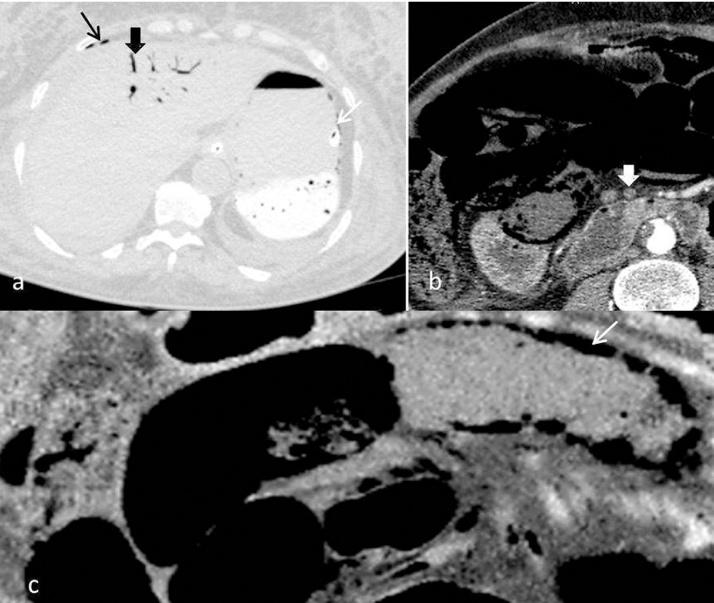

The aim of this study was to report through 13 cases the particularities of abdominal computed tomography (CT) aspects of hepatic portal venous gas (HPVG) and its correlation with patient prognosis.

We analyzed abundance of HPVG and its association with pneumatosis intestinalis (PI) in correlation with fatal outcome using chi-square tests.

Etiologies were mesenteric infarction (n=5), sigmoid diverticulitis (n= 1), septic shock (n=1), postoperative peritonitis (n=1), acute pancreatitis (n=1), iatrogenic cause (n=3) and idiopathic after a laparotomy (n=1). The outcome was fatal in for 6 patients. Abundance of HPV was expressed in total number of hepatic segments involved. The involvement of 3 or more segments was a sensitive sign for lethal outcome with high sensitivity (100%) but it was not specific (50%). Negative predictive value of this sign was 100% (p≤0.005). Positive predictive value of PI for death was 100% (p≤0.001).

Abundance of HPVG is correlated with prognosis. The presence of PI announces poor outcome Negative predictive value of presence of HPVG in 3 or more segments is interesting. Predicting prognosis with CT can help surgeons to assess the most adequate treatment. Iatrogenic causes are increasingly described after interventional radiology procedures with favorable course.

The first etiology radiologists should look for in front of HPVG involving more than 3 hepatic segments and associated with PI is intestinal necrosis which announces a poor prognosis. This study shows that outside of shock situations, HPVG involving 2 or less hepatic segments without PI predicts a good outcome.